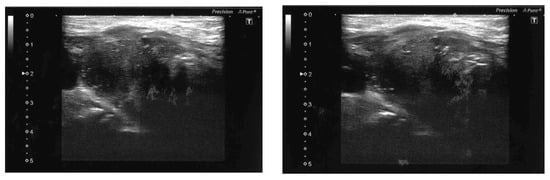

- Zhang, Y.; Xue, S.; Wang, Z.; Jin, W.; Chen, Z.; Chen, G.; Zhang, Q. Thyroid metastasis from breast cancer presenting with enlarged lateral cervical lymph nodes: A case report. World J. Clin. Cases 2020, 8, 838–847. [Google Scholar] [CrossRef]

- Lee, D.H.; Yoon, R.G.; An, J.K.; Woo, J.J. Ultrasonographic Features and the Diagnostic Role of Core Needle Biopsy at Metastatic Breast Cancer in the Thyroid gland: A Case Report. Taehan Yongsang Uihakhoe Chi. 2020, 81, 719–725. [Google Scholar] [CrossRef]

- Jung, H.K.; Kim, B.; Ryu, J.H. Intrathyroid metastasis of breast cancer: Sonographic findings. J. Clin. Ultrasound. 2021, 49, 488–491. [Google Scholar] [CrossRef] [PubMed]

- Hoshi, M.; Jikuzono, T.; Suzuki, S.; Ishibashi, O.; Kawamoto, Y.; Kure, S.; Kawamoto, M.; Ohashi, R.; Sugitani, I. Use of ultrasonographic shear wave measurements to diagnose thyroid metastasis from breast carcinoma. J. Nippon Med. Sch 2022. Epub ahead of print. [Google Scholar] [CrossRef] [PubMed]

- Zhang, K.; Yu, Y.; Zang, Y.; Xu, H.; Lv, B.; Wang, Q. Case report: Unique ultrasound feature of thyroid metastases in occult breast cancer. Front. Oncol. 2022, 12, 970286. [Google Scholar] [CrossRef]